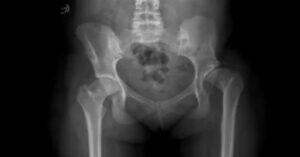

Ameliyat öncesinde hastanın genel sağlık durumu ayrıntılı şekilde değerlendirilir. Gerekli kan testleri ve görüntüleme yöntemleri uygulanabilir. Röntgen veya tomografi gibi tetkikler kırığın yapısını daha net ortaya koyar. Bu değerlendirmeler sayesinde cerrah en uygun ameliyat yöntemini planlayabilir. Operasyon genellikle genel veya spinal anestezi altında gerçekleştirilir.